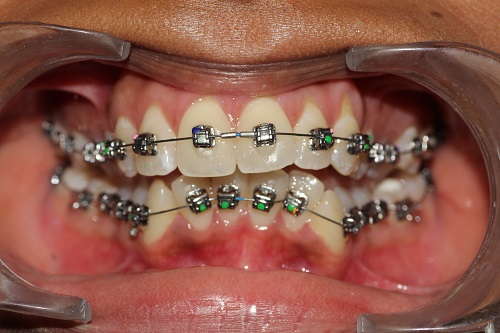

The various treatment offered in the department includes fixed orthodontic treatment with metal, ceramic,self-ligating brackets, treatment with mini-implants, Rapid Maxillary Expansion appliances, orthognathic surgeries to correct facial deformities, distraction osteogenesis procedures with Internal and External distractors, treatment of cleft lip and palate, Pre-surgical Naso Alveolar Moulding on cleft cases, Fixed functional treatment with Forsus, Powerscope, Herbst etc, Lingual Orthodontic treatment, Myofunctional Appliance Therapy, Aligner Orthodontic Treatment ,Myofunctional trainers, Splints- For Temporomandibular joint disorders as well as Class III correctors in growing individuals with appliances such as Tandem Traction Bow Appliance.